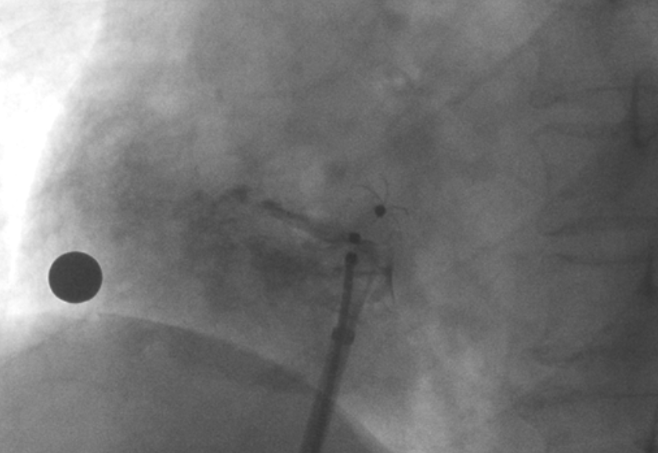

術(shù)中造影顯示患者為PFO且長隧道型,目前市場上已商業(yè)化的PFO封堵器難以滿足該患者解剖結(jié)構(gòu)封堵需求。迪創(chuàng)醫(yī)療自主研發(fā)的OmniSeal PFO封堵器自適應(yīng)性雙盤貼合設(shè)計能廣泛適應(yīng)不同PFO隧道長度的解剖結(jié)構(gòu)和形態(tài),其雙盤外包覆式阻流和隧道內(nèi)填充阻流相結(jié)合的雙重阻流設(shè)計,可為此患者實現(xiàn)有效封堵。與此同時,OmniSeal首創(chuàng)的完全可穿刺式設(shè)計,也為此患者最大程度地保留了房間隔區(qū)域穿刺通道,以實現(xiàn)全兼容未來可能的左心系統(tǒng)二次介入術(shù)。術(shù)終造影和心臟超聲顯示封堵完全、效果良好。作為OmniSeal的首例臨床應(yīng)用,本次手術(shù)的順利完成和優(yōu)異效果充分體現(xiàn)了產(chǎn)品的設(shè)計創(chuàng)新優(yōu)勢。

造影顯示長隧道型PFO